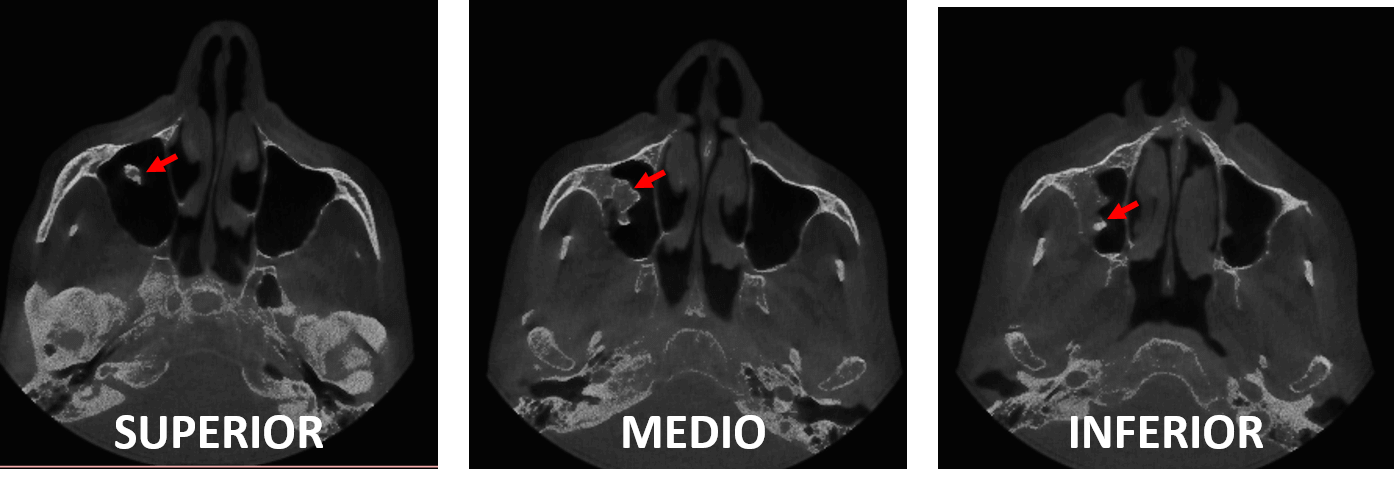

Fig.4

En cortes axiales (Fig.4) se observa la forma irregular de dicha estructura de densidad ósea en el interior del seno maxilar derecho compatible con una tumoración de origen benigno compatible con un Osteoma.